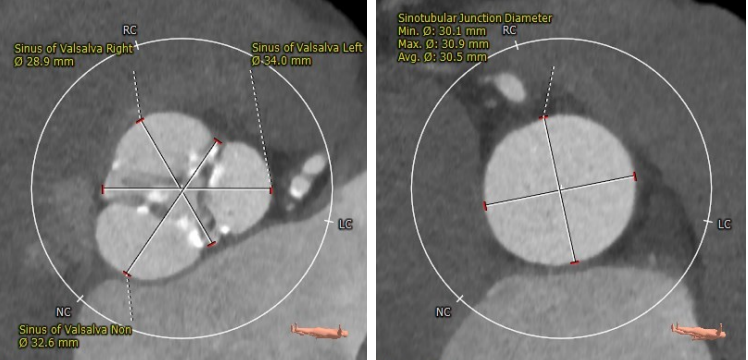

CTA主动脉根部解剖:

患者为三叶瓣,轻度钙化,右冠开口高度较高,升主动脉最宽处约33.2mm,横位心,心脏角度约62°,左室偏小。

Annulus Dimensions ——24.5mm

LVOT——25.5mm

Sinus——32.6*34*28.9mm

Stj——30.5mm

升主最宽处:33.2mm

心脏角度:62°

该病例为三叶瓣,瓣环直径24.5mm,左冠开口高度12.2mm,右冠开口高度17.4mm,升主最宽处达33.2mm,经核心实验室评估后 术中冠脉无堵塞风险,入路内径尚可,计划使用右侧股动脉为主入路,左侧股动脉为副入路。23mm球囊预扩张,使用Venus-A 29瓣膜。